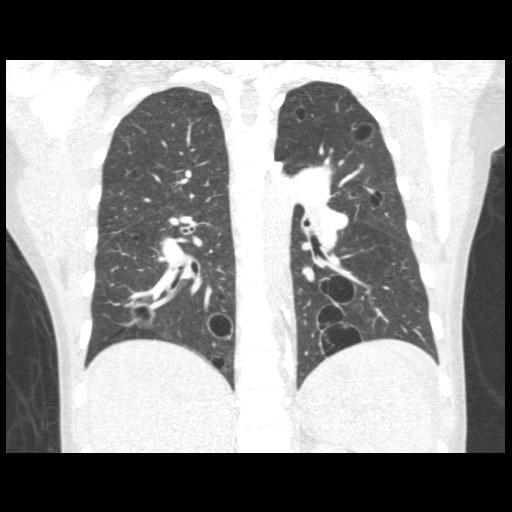

Vital signs and cardiopulmonary exam were normal. Basic labs and EKG were also normal. Due to an elevated D-dimer of 570 ng/mL, she had a CTA chest done.

CXR and CT Chest

What is the most likely etiology of her diffuse cystic lung disease?